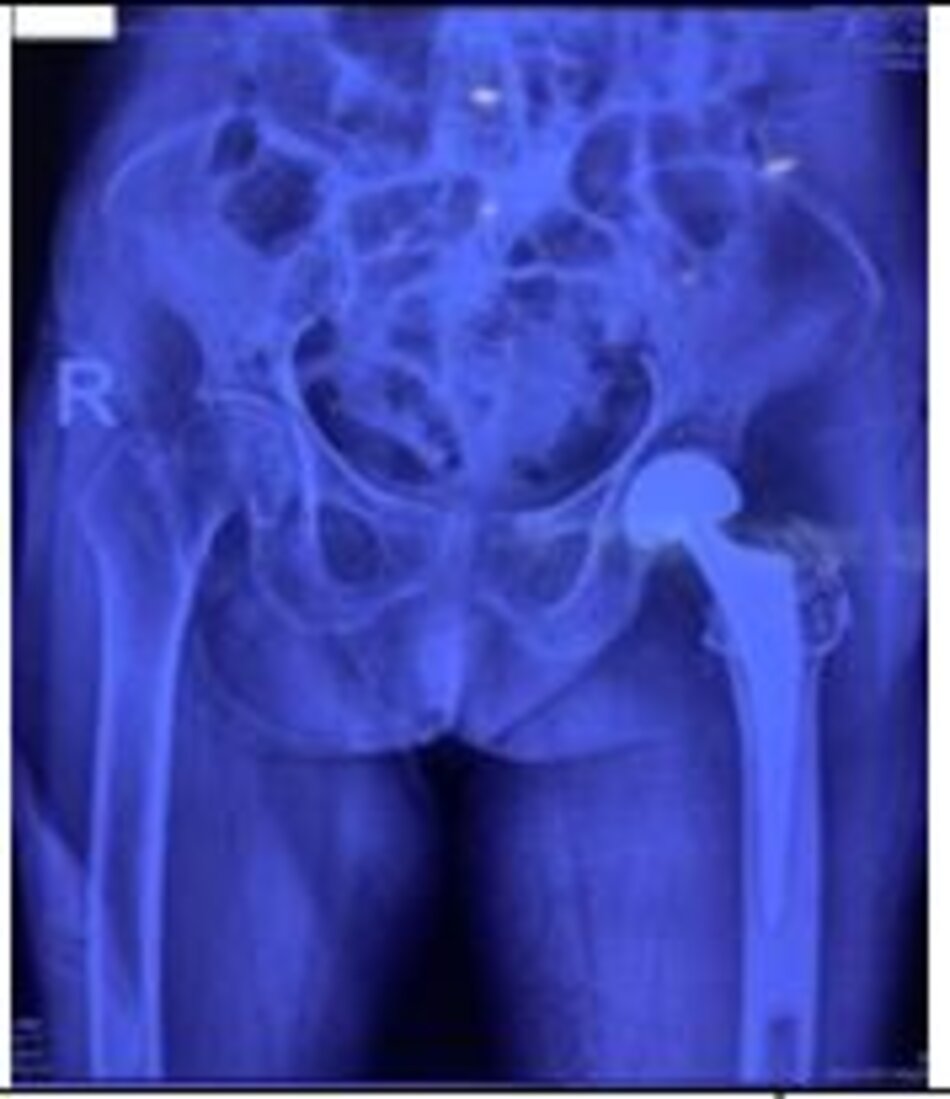

Xquang trước mổHình ảnh hoại tử chỏm xương đùi trái

Xquang trước mổ. Hình ảnh hoại tử chỏm xương đùi trái

Xquang sau mổ. Hình ảnh khớp háng trái nhân tạo